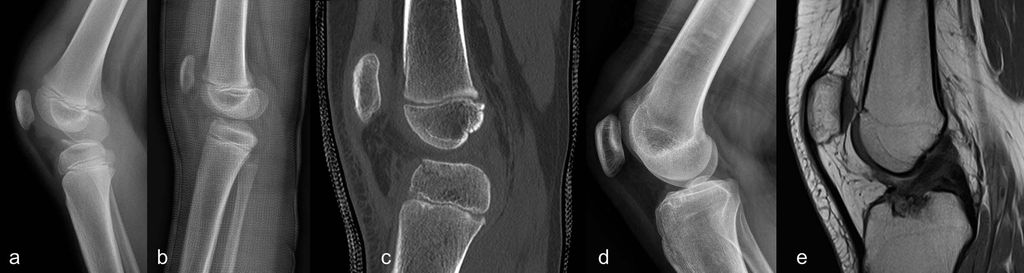

Typ-1- und Typ-5-Verletzungen können auch als knöcherne Avulsionverletzungen auftreten, wobei die distalen knöchernen Ausrissfrakturen häufiger sind. Dabei kommt es bei Kindern mit noch unreifem Skelett noch vor einer Ruptur des VKB zu einer Avulsion der noch nicht vollständig ossifizierten Eminentia intercondylaris. Die Einteilung der tibialen VKB-Ausrissfrakturen erfolgt anhand des Dislokationsgrads nach Meyers-McKeever (Abb. 1).

Abb. 1: Klassifikation der Eminentiafrakturen nach Meyers und McKeever: a) Grad 1 = keine oder minimale Dislokation des Fragments; b) Grad 2 = Dislokation des Fragments ventral; c) Grad 3 = vollständige Dislokation; d) Grad 4 = vollständig disloziertes, in sich frakturiertes Fragment (aus Stotter und Reuter 2022, mod. nach Meyers und McKeever)44

Die konservative Behandlung von tibialen Ausrissfrakturen erfolgt in einer Oberschenkelgipshülse (Abb. 2). Die Ruhigstellung erfolgt in Überstreckung oder leichter Flexion und die Reposition wird initial und nach Belastungsaufbau nach etwa 1 Woche radiologisch überprüft. Bei sekundärer Dislokation wird die Indikation zur Operation gestellt.

Abb. 2: McKeever-Grad-2-Verletzung bei einer 7-jährigen Patientin mit konservativer Behandlung (a); Repositionsbilder in der Oberschenkelgipshülse in leichter Hyperextension (b), korrekte Reposition im CT (c); Ausheilungsbilder nach Wachstumsabschluss zeigen ein intraossäres Ganglion bei regulärem Verlauf des vorderen Kreuzbandes (d,e)